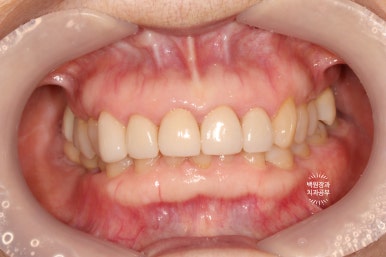

이렇게해서 두 번 수정한 앞니 지르코니아 크라운입니다.

처음에 비해 훨씬 가지런해지고 여성스러운 모양을 가진 치아로 완성되었네요!

치료 전과 후를 비교해보았을 때, 대문니에 있던 세로 금이 깔끔하게 해결되었고 밝아진 치아의 색상은 훨씬 더 환한 인상을 주게 되었습니다.

저희 치과의 카메라가 달라져 비록 같은 색감을 내고 있지는 않으나, 2차 충치나 크라운의 파절 없이 깔끔하게 유지되고 있는 앞니 지르코니아 크라운들을 보실 수 있습니다!!

좌측과 우측 측면에서 보아도 아주 깔끔하게 유지되고 있는 앞니 지르코니아 크라운들입니다.

매우 흡족한 결과입니다 :)